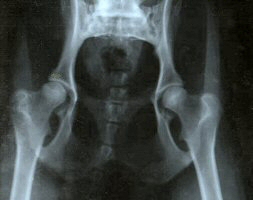

Good Hip Score Poor Hip Score

X Ray showing joints yielding a good hip score. The balls (femoral heads) fit tightly into deep, rounded sockets (acetabulae).

Hip dysplasia is a partial dislocation of the ball joint resulting in lameness when dogs are severely affected. It is largely inherited, so can only be reduced by testing and careful selection of breeding stock. Both boxer parents should have test scores less than 14.89, which is the average for the breed in New Zealand. However, positive results from the parents do not guarantee low scores for all their puppies, but the risk of problems is much less than if the parents are not tested. As part of a long term breeding plan, as many dogs as possible in a line should be tested to establish a significant average score. Dogs must be over 12 months old before they can be tested.